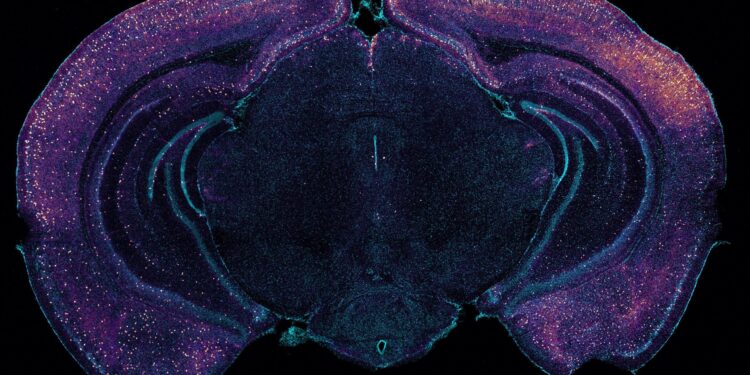

Vibrant staining highlights VIP-expressing interneurons on this coronal cross-section of a mouse mind. The neurons could assist drive glymphatic clearance of amyloid by way of the discharge of peptides. Credit score: Tsai Laboratory/MIT Picower Institute

The RNA sequencing knowledge additionally revealed that upon gamma sensory stimulation a subset of neurons, referred to as “interneurons,” skilled a notable uptick within the manufacturing of a number of peptides. This was not stunning within the sense that peptide launch is thought to be depending on mind rhythm frequencies, nevertheless it was nonetheless notable as a result of one peptide specifically, VIP, is related to Alzheimer’s-fighting advantages and helps to control vascular cells, blood circulate and glymphatic clearance.

Seizing on this intriguing consequence, the group ran assessments that exposed elevated VIP within the brains of gamma-treated mice. The researchers additionally used a sensor of peptide launch and noticed that sensory gamma stimulation resulted in a rise in peptide launch from VIP-expressing interneurons.